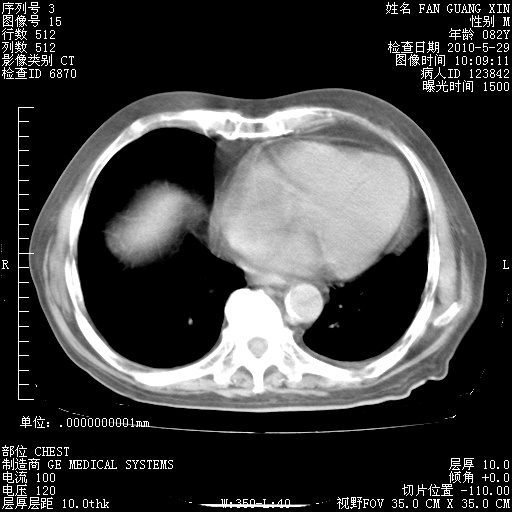

再治疗10天后的肺部CT

再治疗10天后的肺部CT 纵膈窗

肺部体征:呼吸25次/分,心率100次/分,呼吸音增粗。无干湿罗音。

血常规:15.36×10 [sup]9[/sup]/L  N0.92  L0.036  M0.045 ESR 27mm/h。

血生化:白蛋白33.30g/L  球蛋白23.67g/L  CRP 32.82mg/L 肝肾功能正常。电解质正常。

从白细胞总数和中性比例看好像合并感染。肺部纹理好像比上次多,支气管炎?其他感染?

阅读此次胸部CT,肺间质渗出性改变较入院时有吸收。目前从体温、白细胞、中性分叶明显增高,肯定存在细菌感染(发生医院感染哦,若无消化道及泌尿系统等感染的依据,肺部感染可能大)。若你院头孢哌酮舒巴坦钠耐药率较高,同意你的方案,若48小时体温仍高,可考虑使用碳青霉稀类抗菌药物,同时可予超声雾化、注意滴数时加大液体量。白蛋白33.30g/L较低哦,需加强营养等支持治疗。